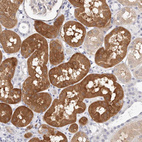

Immunohistochemistry analysis in human cerebral cortex and skeletal muscle tissues using HPA030387 antibody. Corresponding GDA RNA-seq data are presented for the same tissues.